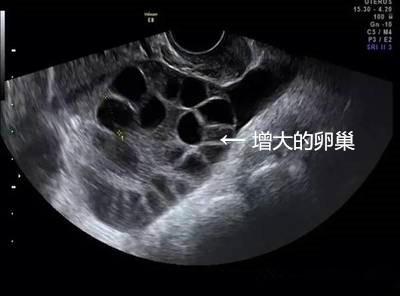

取卵成功后,中介就没有再联系琳琳。但取卵5天后,琳琳出现持续性下腹胀,还有十分明显的胸闷症状。她再次联系卖卵中介,但对方拒绝承担责任,还威胁琳琳不要再纠缠。琳琳到我省这家妇幼保健院就诊,B超提示腹腔内大量积液,胸腔少量积液,卵巢增大超过3倍以上,考虑是卵巢过度刺激综合症,被收治住院。

由于腹腔内积液增多,肚子大了一圈,琳琳无法平躺,入眠困难,进食困难,非常痛苦。在先后进行2次腹腔穿刺抽出腹水后,症状才得以缓解,最后住院10天左右才得以出院。

林医师介绍,女性卵巢每个月都会有一批基础卵泡生长,但其中只有1到2颗会成熟。如果用促排卵针来刺激所有卵泡都成熟,那么卵巢就会变大。卵泡越多,卵巢被撑得越大。尤其是年轻女性,卵巢条件好,基础卵泡多,用高剂量药物促排后,若获卵大于15颗,卵巢过度刺激的风险就大。因此在杭妇院生殖医学中心给不孕不育女性做试管婴儿前,给患者做促排卵也要求少于15颗,正是为了避免女性得卵巢过度刺激综合征。

1、卵巢过度刺激综合征,尤其是瘦小、年轻的女孩子更容易得。卵巢增大导致卵巢壁毛细血管通透性增大,体液积聚于组织间隙,进而使引起腹腔积液、胸腔积液,甚至会导致血栓,危害生命。